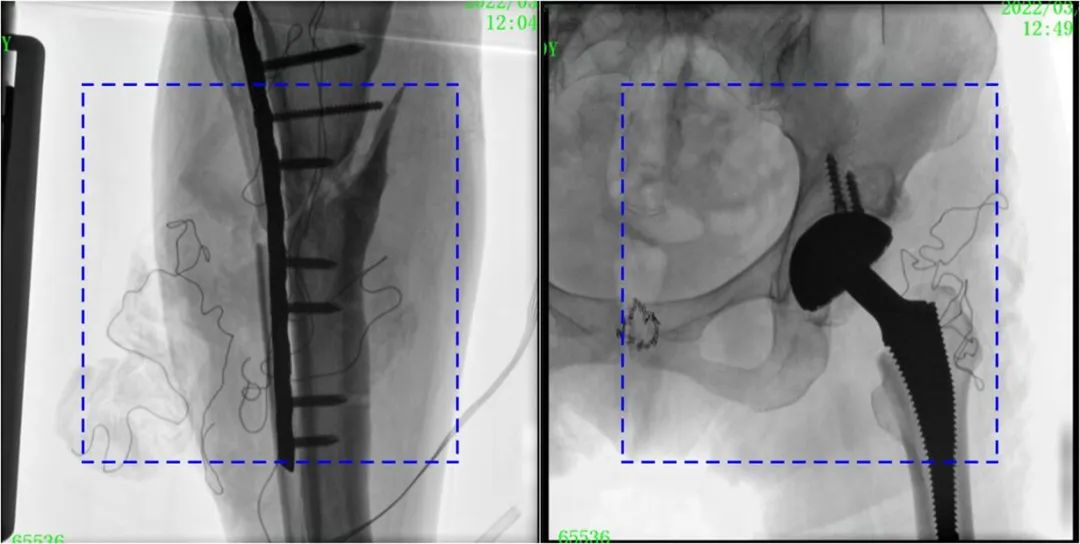

术中定位准确、出血量少,术后影像显示股骨移位纠正,恢复良好力线,手术效果良好。

PLX119C临床图像与传统图像对比

注:蓝色虚线内为传统21CM×21CM平板的成像区域。